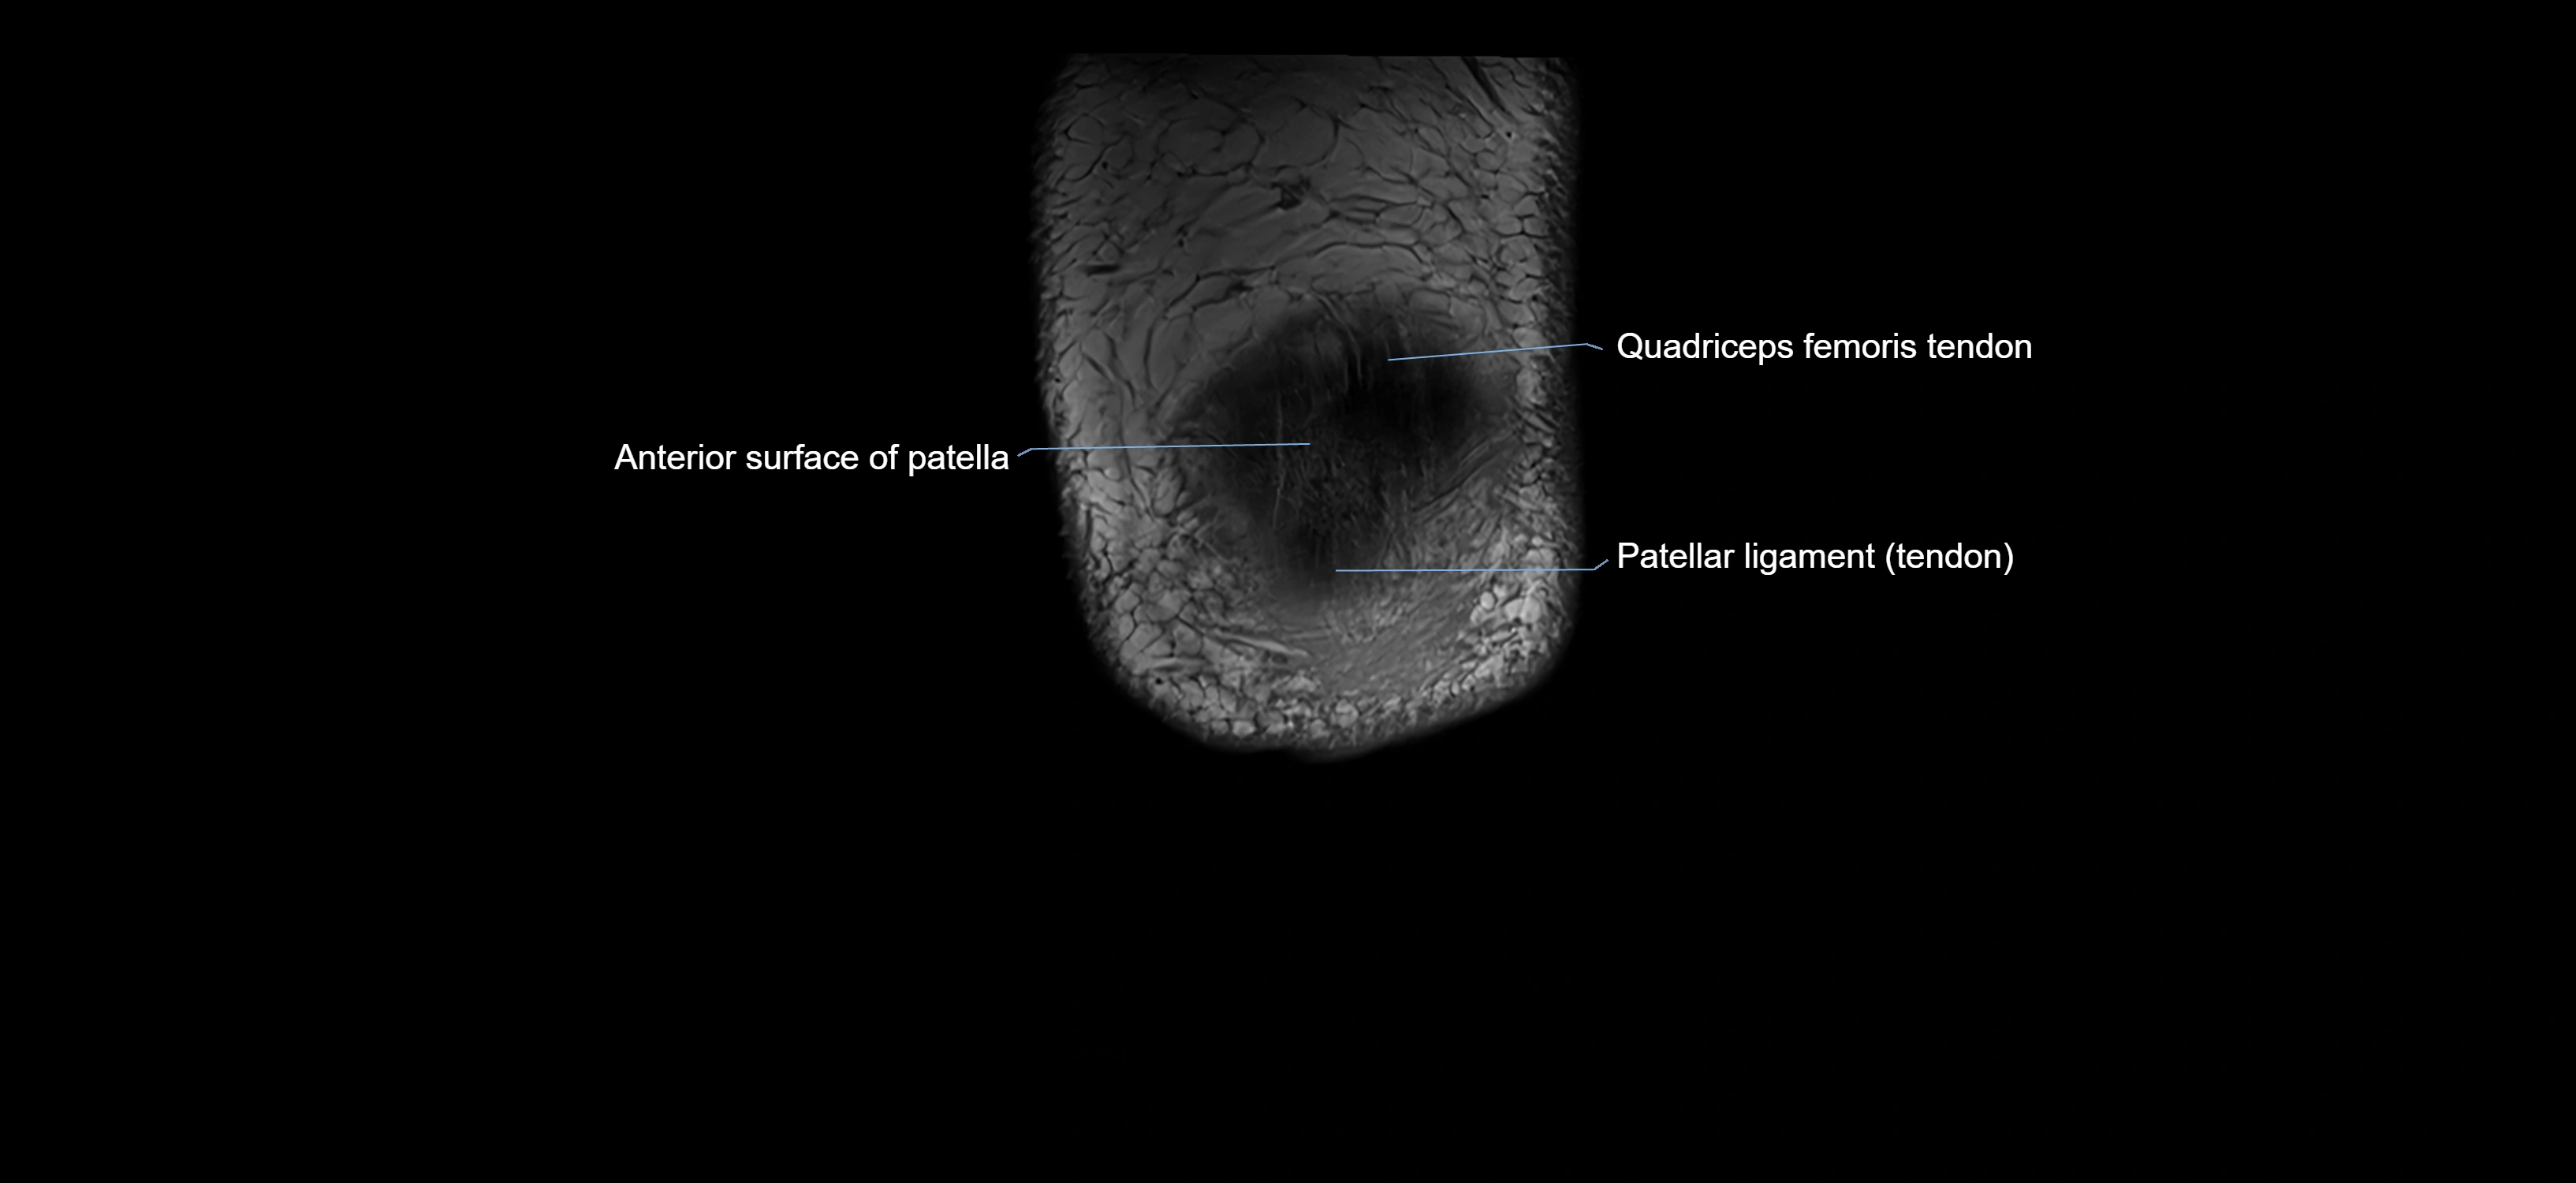

- Patella

- Patellar articular cartilage

- Patellar tendon (patellar ligament)